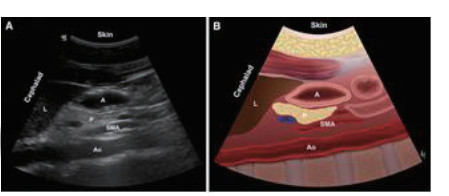

1.2.1 ①胃窦超声评估利用床旁超声机Sonosite M-Tube进行检测,利用2~5 MHz凸阵探头,患者取仰卧位或右侧卧位(因病情危重无法右侧卧位者取仰卧位),床头抬高30~45°,探头方向与身体纵轴平行,在剑突下于正中矢状线右侧获取清晰胃窦部超声[1],见图 1。

| 图 1A 胃窦超声检查部位 |

| 图 1B 胃窦超声切面及示意 |